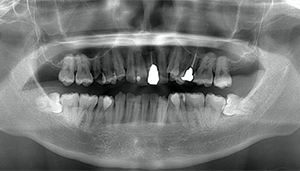

CT

- Before

- After

CTで親知らずと神経(下歯槽管)の位置を確認しました。

親知らずと神経は一定の距離があり、麻痺などのリスクがほとんどないと判断できます。

口腔内

半埋伏の親知らずでした。3糸縫合しました。